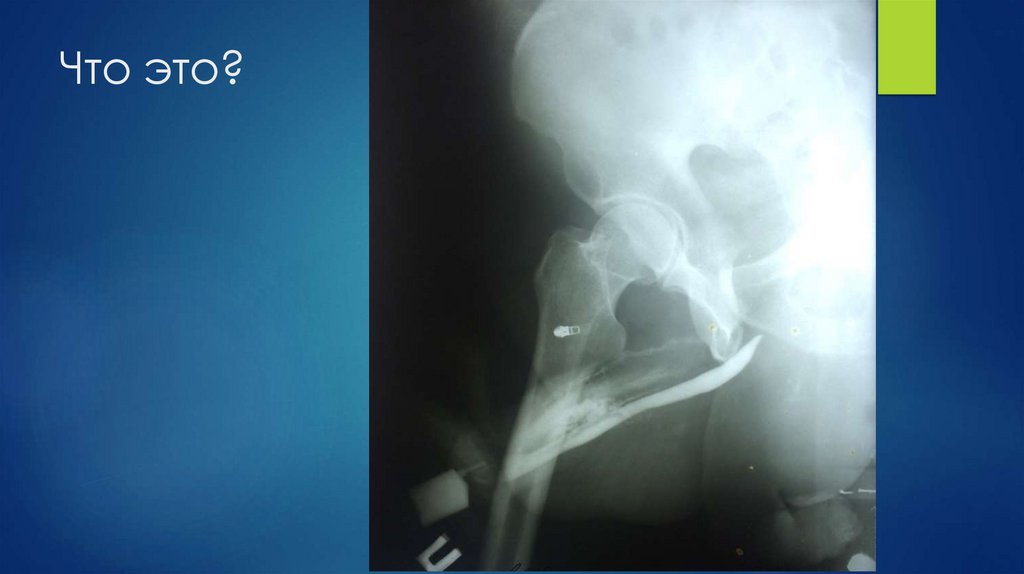

56. Что это?